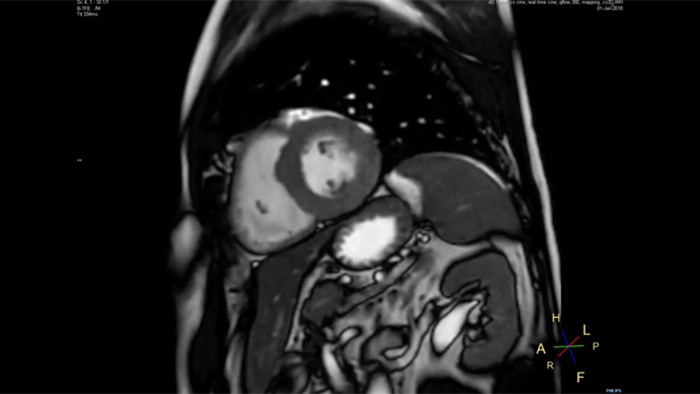

Philips Compressed SENSE verkürzt die Zeit, die ein Patient im MR-Scanner verbringt. Außerdem kann mit Compressed SENSE die Atemanhaltezeit verkürzt werden, was die Patientencompliance bei einem MR-Scan fördert.

4,8 s Atemanhalten

Da kurze Atemanhaltephasen einfacher für unsere Patienten sind, kommt es jetzt fast nicht mehr vor, dass Patienten den Atem nicht lang genug anhalten. In unserer Einrichtung sind bei Kardio-MRTs jetzt weniger Atemanhaltephasen nötig, oder die nötige Dauer der Atemanhaltephasen hat sich verkürzt.“

Dr. Takashi Koyama, MD, PhD, diagnostischer Radiologe und Leiter des Radiologiezentrums und der diagnostischen Radiologie, Kurashiki Zentralkrankenhaus, Japan

Eine Atemanhaltephase von 15 bis 16 Sekunden ist für viele Herzpatienten schwierig. Mit Compressed SENSE haben wir jetzt Protokolle, in denen diese Zeit auf unter 10 Sekunden reduziert wurde. Das ist für die Patienten viel einfacher. Die Patienten sind dann mit dem Verfahren auch viel zufriedener.“

Trevor Andrews, Ph.D., MR-Physiker, University of Vermont Medical Center, USA